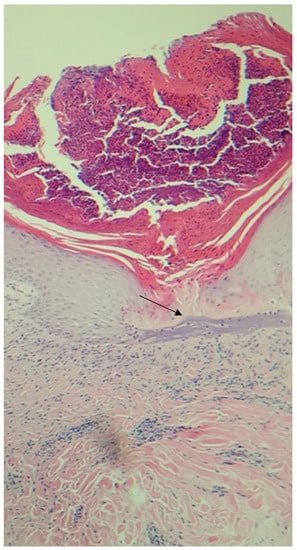

2. Case Report